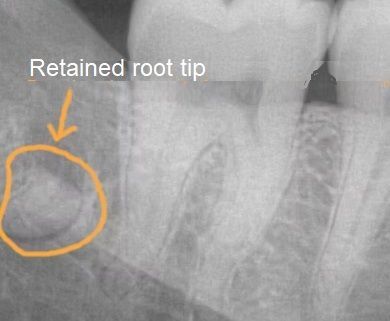

When it comes to tooth extractions, most patients assume that once the tooth is removed, the problem is solved. However, sometimes a small portion of the tooth root, known as a

root tip, can remain in the jaw. While in some cases, leaving a tiny root fragment may seem harmless, there are critical situations where it must be removed to protect your oral health.